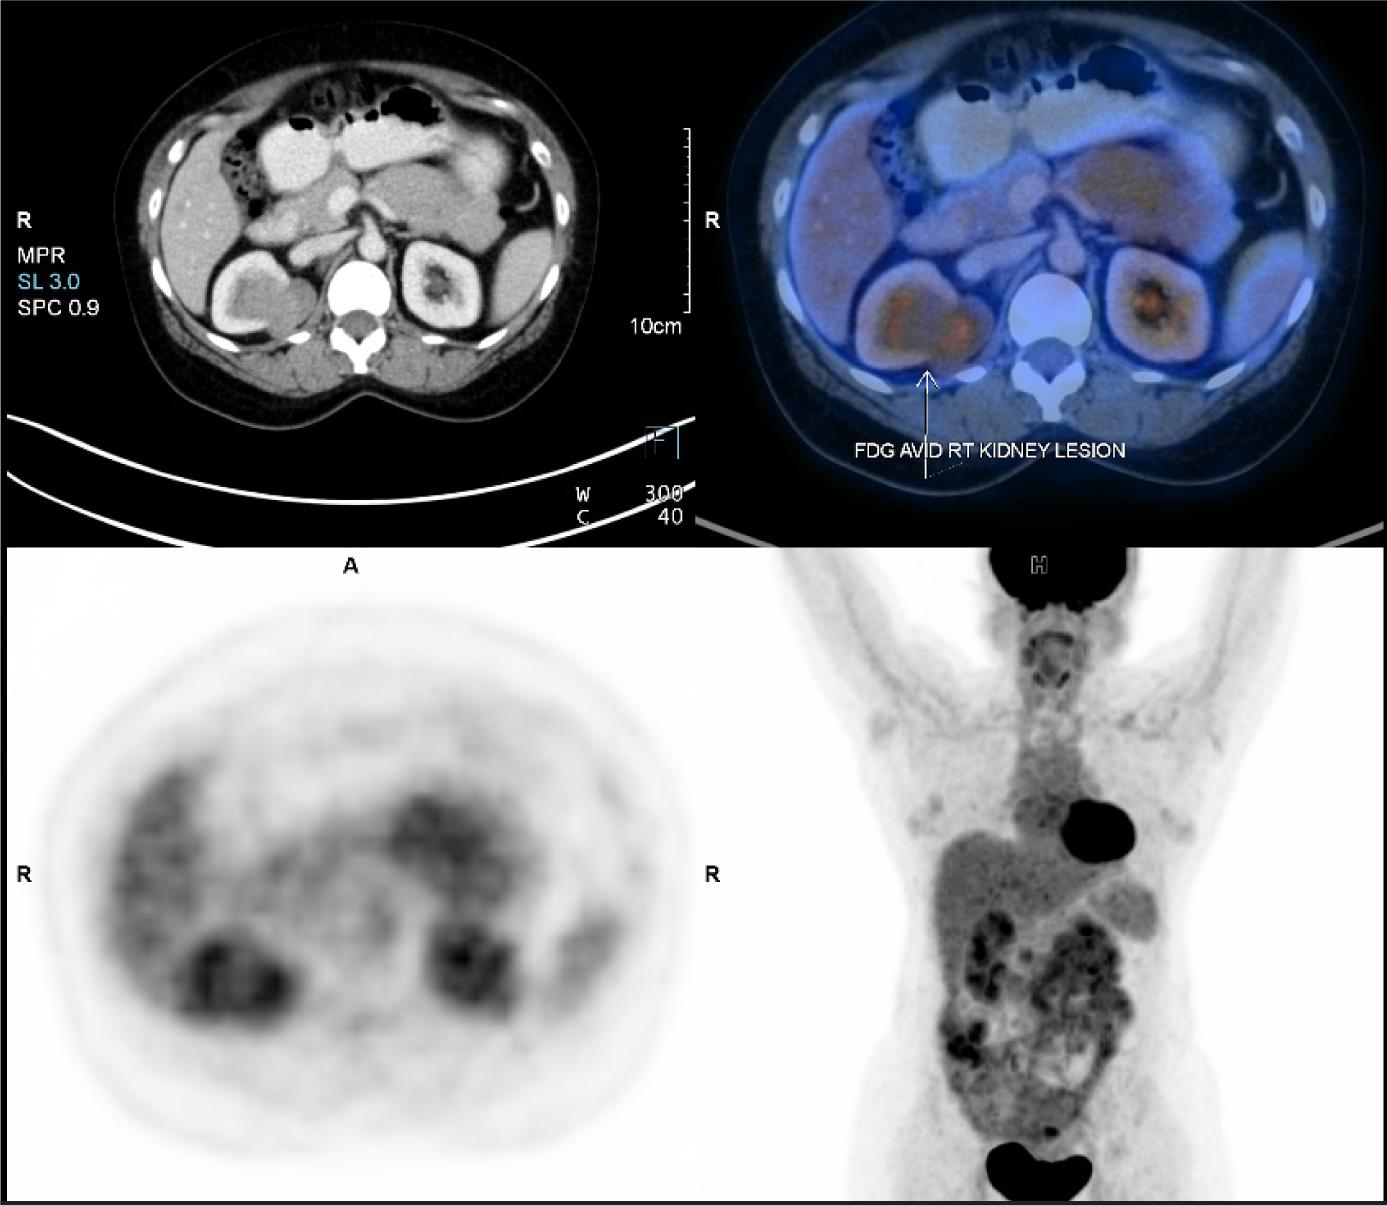

A 48-year-old female patient came with an incidentally detected right renal mass during evaluation for menorrhagia. Ultrasound evaluation for the same revealed a right renal mass. This was further evaluated with a dedicated computed tomography (CT) scan of the abdomen, which showed a solid cystic mass lesion in the right kidney’s upper pole, which was located posteromedially and measured 57*45*34 mm with obvious enhancement. There were also multiple enlarged retrocaval and aortocaval nodes, the largest measuring 25* 12 mm (Figure 1). Her serum creatinine was 0.8 mg/dL and her hemoglobin was 11 g/dL. The uterus showed evidence of multiple fibroids. She did not have any flank pain, lower urinary tract symptoms, or hematuria. She had no comorbidities or addictions. She, however, did have a family history of breast cancer. She underwent metastatic workup by an FDG positron emission tomography (PET) CT scan (Figure 2), which showed a metabolically active heterogeneously enhancing lobulated solid cystic lesion in the right kidney along with metabolically active right renal hilar and aortocaval lymph nodes. No other areas of metastasis were found.

Figure 2: FDG PET CT showing uptake in the right renal mass.

The most widely used functional imaging technique for cancer detection is fluorodeoxyglucose-PET (FDG-PET). For well-differentiated NETs, In-pentetreotide was more sensitive than FDG-PET, whereas it showed greater sensitivity for poorly differentiated NETs (14). In the review by Andreas et al., FDG PET was found to be even more reliable than KI65 classification (15). FDG-PET is frequently employed to assess tumor metabolism in cancer patients in different stages of the disease (16).